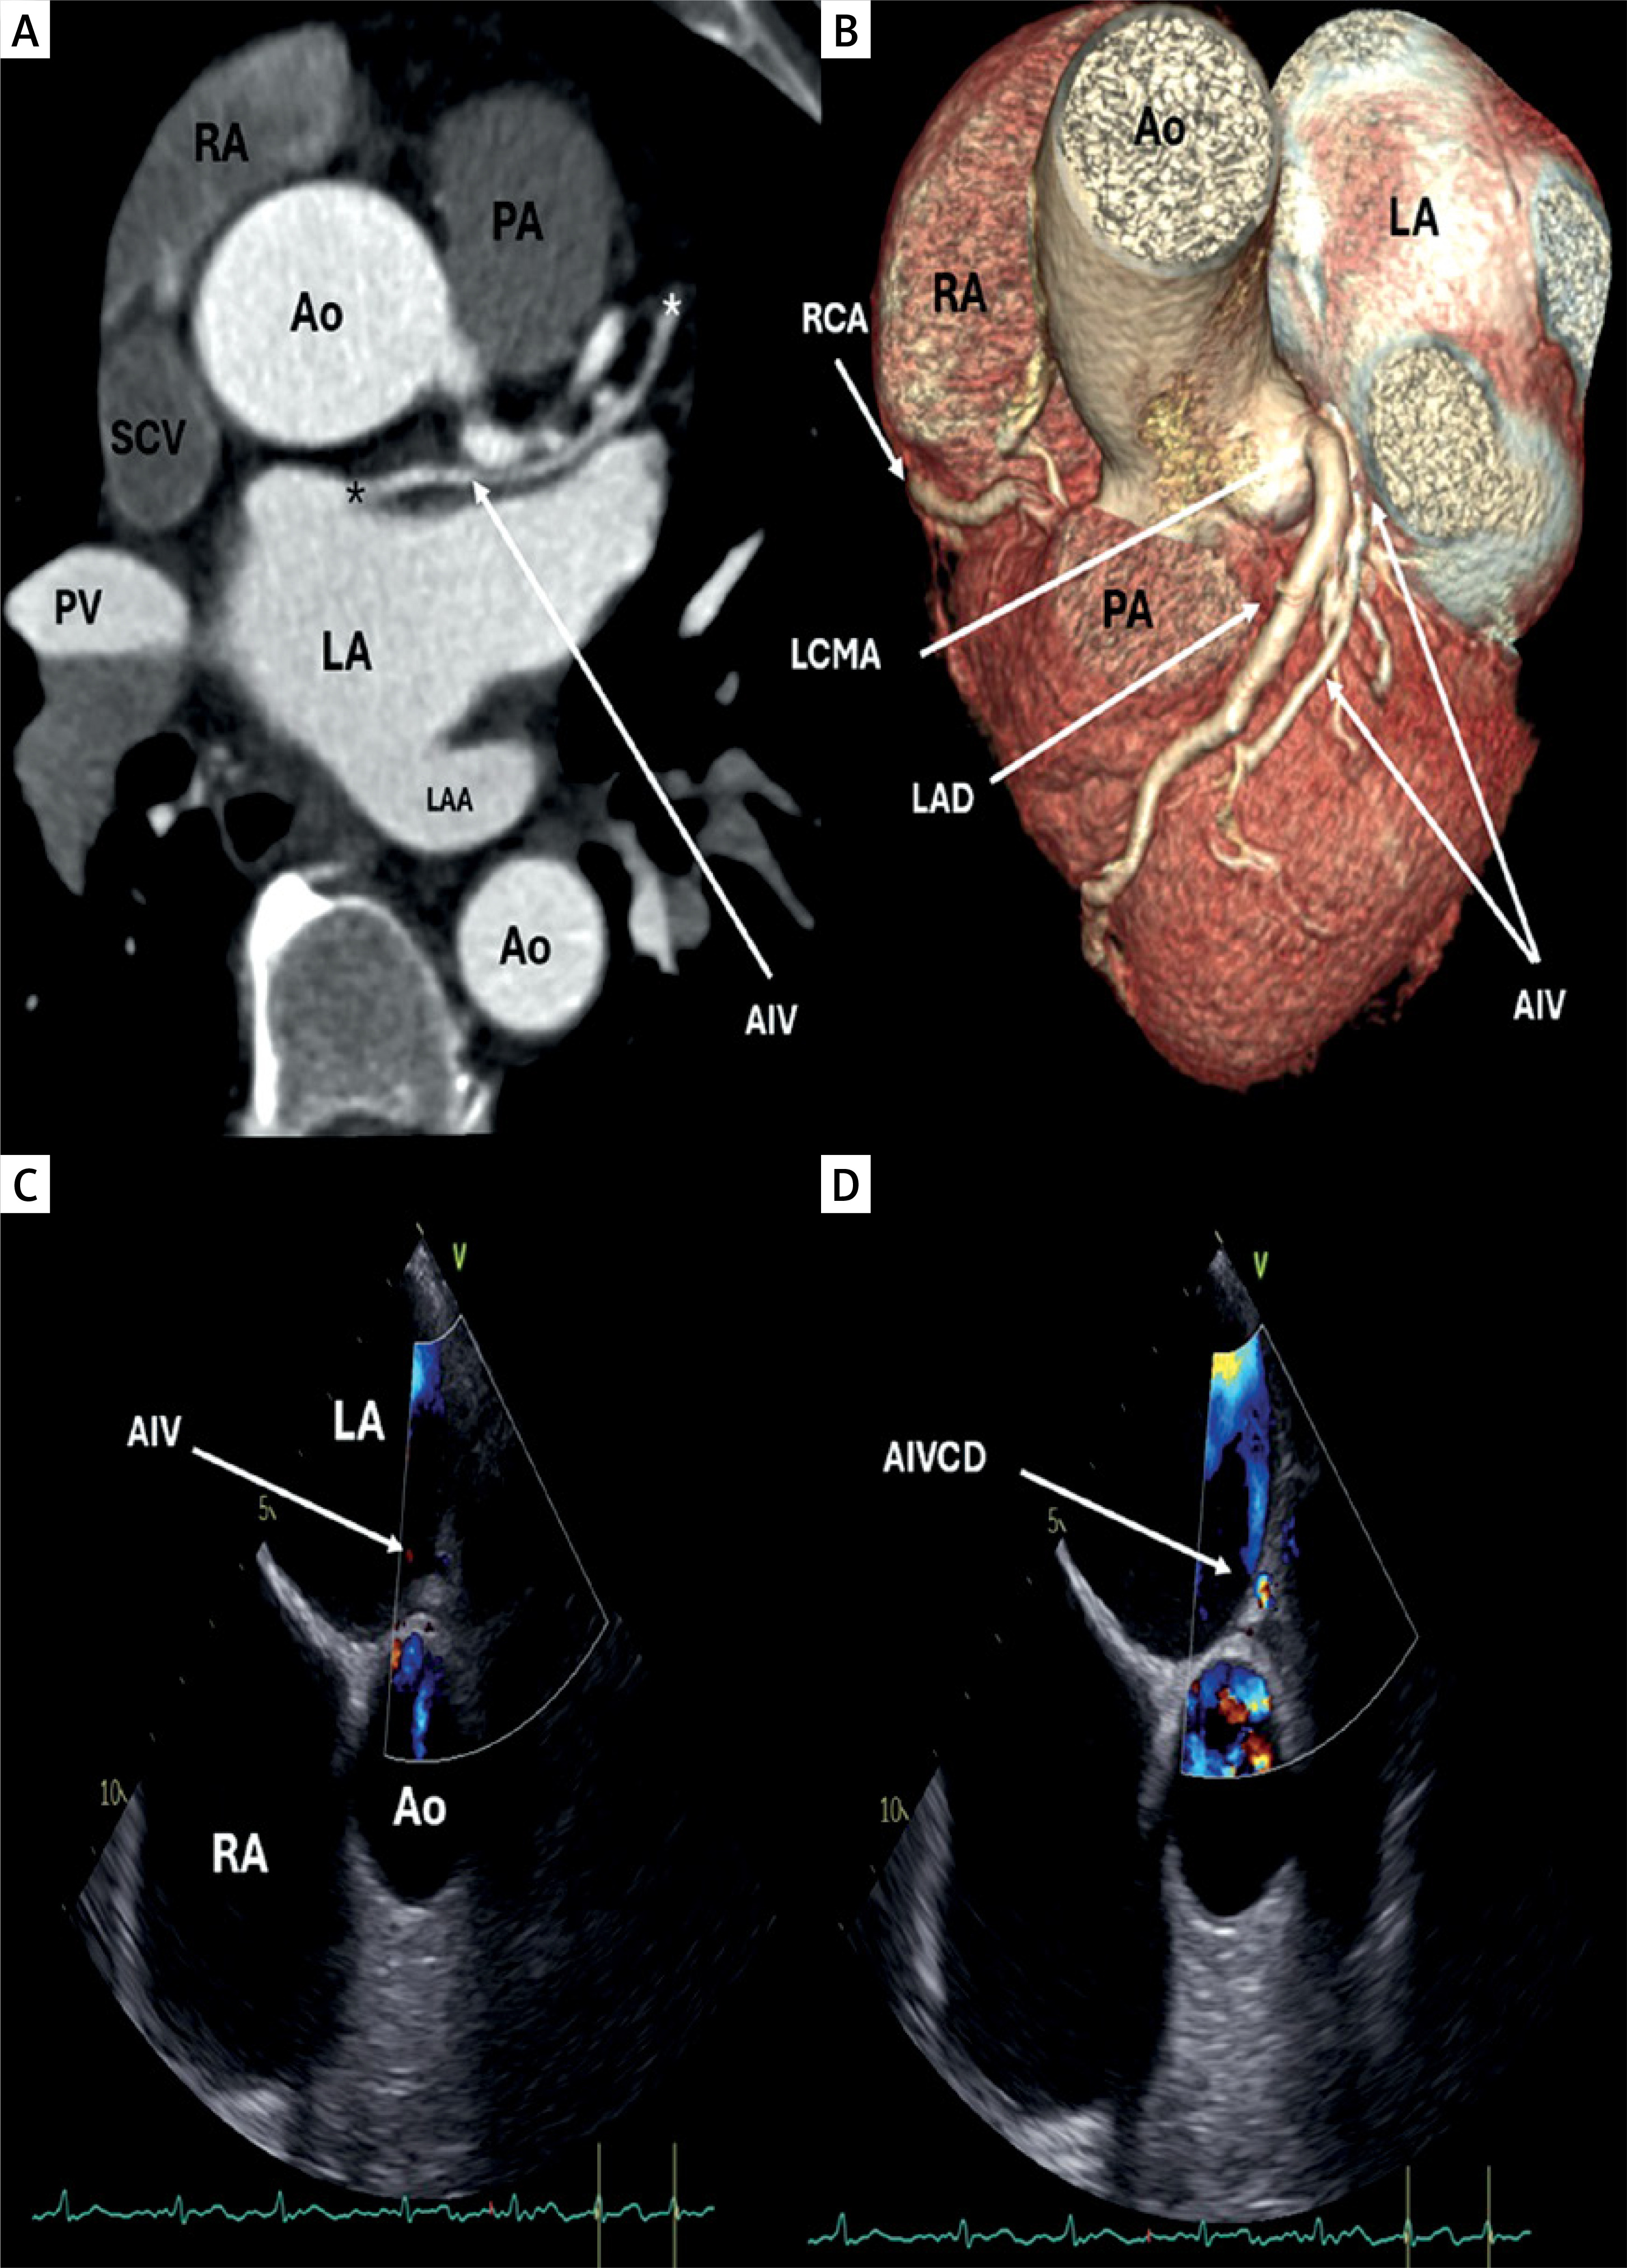

An electrocardiography-triggered MSCT of the coronary arteries was performed using a 128-slice Somatom Flash Dual Source Siemens device. MSCT of the coronary arteries did not reveal significant lesions. However, the multiplanar reconstruction and 3D images revealed the anterior interventricular vein (AIV) running parallel to the left anterior descending artery (LAD) in the interventricular sulcus. The AIV is in close contact with the left main (LM) coronary artery at the bifurcation into the LAD and left circumflex arteries, and it drains into the left atrium (LA) on the anteromedial wall (Figures 1 A, B). The remaining venous system shows normal anatomical configuration, with the coronary sinus draining into the right atrium at the expected position, along with the presence of the semicircular Thebesian valve at the same level as the Eustachian valve. Following the MSCT of the heart, a transesophageal echocardiographic examination (TEE) was conducted, which revealed the drainge point of the AIV into the LA (Figure 1 C). Furthermore, color Doppler confirmed the flow through the AIV (Figure 1 D).

Figure 1

A – Multi-slice computed tomography (MSCT) axial 2D reconstruction of the left atrium (LA), showing the anterior interventricular vein (AIV) originating from the left ventricle (LV) (white asterisk), draining into the LA (black asterisk); B – MSCT 3D reconstruction showing the relation between the left anterior descending artery (LAD), left main coronary artery (LMCA), and AIV. C – Transesophageal echocardiography showing drainage point of the AIV into the LA. D – Color Doppler confirming flow through the AIV

RA – right atrium, Ao – aorta, PA – pulmonary artery, SCV – superior vena cava, PV – pulmonary vein, LAA – left atrial appendage, AIVCD – anterior interventricular vein color Doppler.